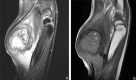

Non-traumatic myositis ossificans circumscripta at elbow joint in a 9-year old child

Myositis ossificans circumscripta (MOC) is a kind of self-localized, benign and tumor-like lesions often seen in adults, with approximately 75% of cases caused by trauma. We reported a case of non-traumatic MOC occurred at the elbow joint in a 9-year old child and it has been excised by surgery. After 18 months follow-up, a favorable outcome has been achieved with the Broberg-Morrey score of 100. We suggest that surgical resection should be done as soon as the diagnosis is confirmed.